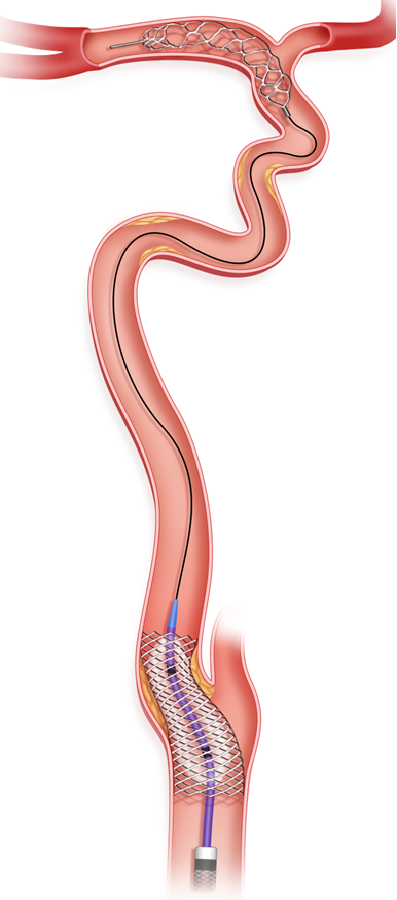

撤出微导丝,在微导管引导下将5.0*35mm Syphonet®取栓支架送至左侧大脑中动脉M1段,防止血栓逃逸,起到保护作用。

撤出微导管,沿5.0*35mm Syphonet®取栓支架导丝送入2.0*20mm Emerge球囊到达左侧颈内动脉闭塞段远端,充盈球囊至8atm,抽瘪球囊,从远端开始球囊扩张,直至颈内动脉起始处。

步骤一:释放Syphonet®取栓支架远端保护。

微导丝、微导管突破闭塞段后,将Syphonet®取栓支架跨越M1段与颈内动脉末端释放,起到颅内远端血管的保护作用。

沿Syphonet®取栓支架输送导丝送入小直径的球囊扩张导管(2mm-2.5mm),由远及近依次对可疑病变部位进行扩张,后再次足量、足压力造影,明确闭塞段内原始病变部位、继发血栓部位和假性闭塞部位。

步骤四:球囊/支架血管成形。

选取合适的球囊扩张导管扩张残余的严重狭窄部位。在出现明显限流性夹层、斑块回缩明显限制前向血流的部位,可考虑经Syphonet®取栓支架输送导丝送入支架系统,支架释放后进行球囊后扩张以提高支架贴壁性,降低再狭窄和再闭塞率。